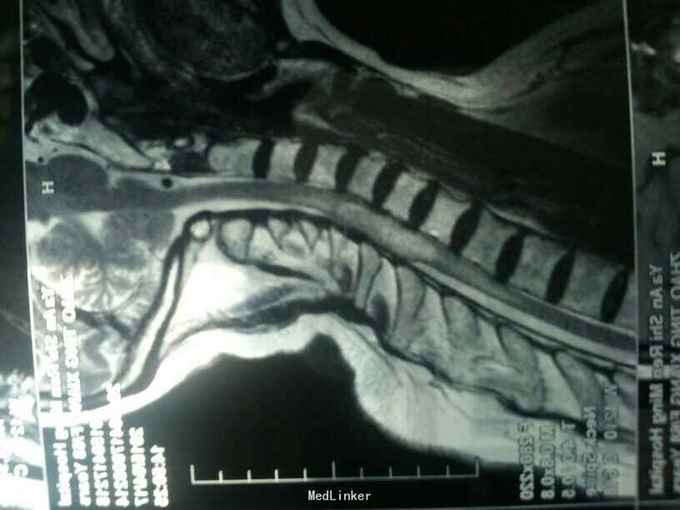

脊髓内肿瘤

腰背部疼痛伴双下肢无力10月

双下肢肌力2~3级。

诊断:颈4~胸1髓内肿瘤 在全麻下行髓内肿瘤摘除术,手术顺利。

术后右下肢肌力2级,左下肢4级。